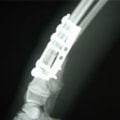

症例3:キルシュナーワイヤーのピンニングによる整復

ペルシャ猫 11ヶ月齢 雄

他院にて左大腿骨遠位の成長板骨折(salter-harrisⅠ型)が認められており、治療相談を目的として来院。当院にて、キルシュナーワイヤーを用いたピンニングにより骨折部位の整復を行いました。術後の経過は良好で、現在も経過観察中です。

術前レントゲン

術後レントゲン

Arthrex社のターゲティングデバイスを用いてピンニングの位置を調整することで、確実な固定を行っています。当院ではこの手術器具以外にも、人の手術にも使用される様々な器具を導入し、手術精度を高め、また医療メーカーと新しい器具の開発、試作にも取り組んでおります。